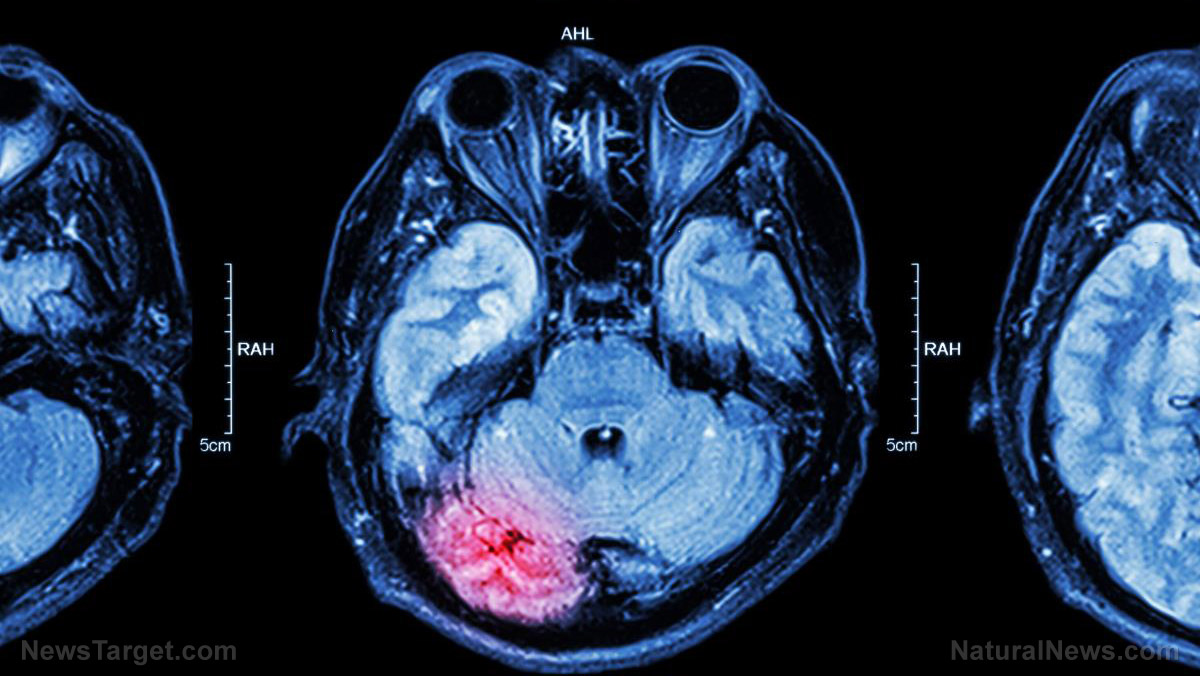

SHOCK: Brain cooling does not benefit people who have a brain injury

(Natural News) Accident victims who suffer a traumatic brain injury usually undergo prophylactic hypothermia (“brain cooling”) in order to protect the fragile organ from further harm. However, a new Australian-led study has concluded that this practice does not actually benefit the patient, reports a The BMJ news article. Cooling the brain was previously believed to decrease the harmful...